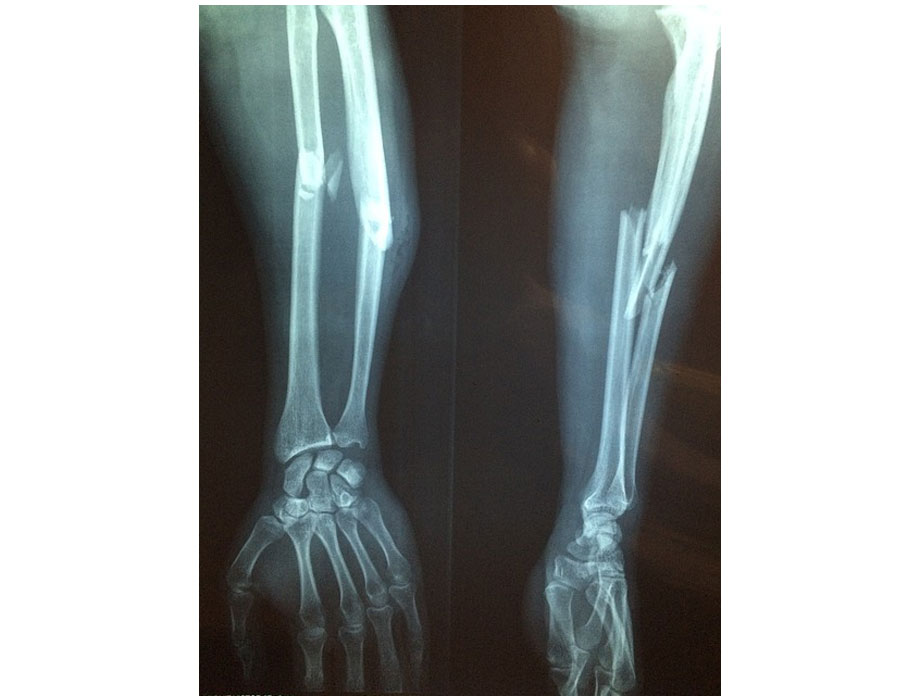

Una de las principales amenazas durante el envejecimiento es la pérdida de masa ósea, que puede derivar en fracturas por fragilidad. Estas fracturas, particularmente de cadera o columna, afectan la movilidad, la independencia y la calidad de vida de millones de personas en todo el mundo. Mientras que en México, tan sólo en el IMSS se atendieron más de 10 mil cirugías por fractura de cadera en 2022.

Las complicaciones asociadas a la fractura de cadera incluyen trombosis por inmovilidad, infección de vías urinarias, úlceras, pérdida de masa muscular, desnutrición e incluso puede llevar a la muerte del paciente. Por ello, cuidar los huesos debe verse como una inversión prioritaria desde la juventud.